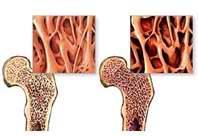

Сочетание остеопороза и остеохондроза

Причиной остеопороза у женщин является недостаток половых гормонов, который возникает в менопаузу (после прекращения менструаций) или по другим причинам (хирургическим).

Что происходит?

Недостаток половых гормонов вызывает потерю костной массы. Утрата губчатой части костной ткани по сравнению с компактной приводит к появлению переломов и деформации тел позвонков и дистального отдела лучевой кости. Снижение высоты позвонков и увеличение переднее задней кривизны в месте перелома приводят к увеличению искривления позвоночника.

Потерю костной массы можно предотвратить за счет гормонального лечения и приема кальция. Кальций содержится в молочных продуктах, рыбе, фасоли, зелени. Имеется много различных препаратов, содержащих кальций. Но всасывание и переработка кальция в организме не возможна без витамина Д. Однако чрезмерное употребление витамина Д может быть вредным для организма. Кроме того, таблетки кальция противопоказаны больным с мочекаменной болезнью.